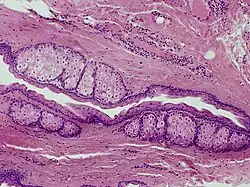

Steatocystoma multiplex is a benign, autosomal dominant congenital condition resulting in multiple cysts on a person's body. Steatocystoma simplex is the solitary counterpart to steatocystoma multiplex.[2]

Steatocystomas are thought to come from an abnormal lining of the passageway to the oil glands (sebaceous duct).